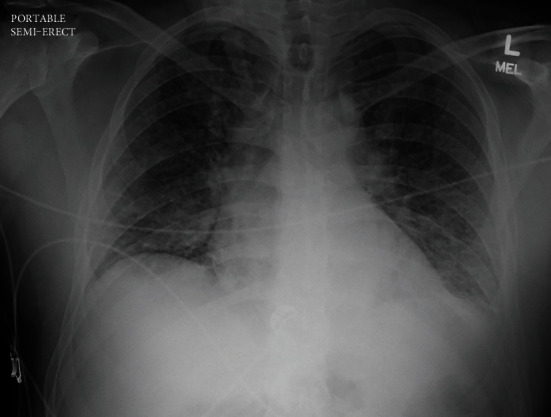

West Nile Virus (WNV) myocarditis is nearly fatal, according to the current medical literature. We report a previously healthy 37-year-old Caucasian male who presented to our facility with two days of progressive lower extremity weakness, fever, edema, and shortness of breath found to have left ventricular global hypokinesis with an ejection fraction of less than 25%, consistent with acute viral myocarditis. He also has concomitant WNV meningoencephalitis due to his altered mentation. He was found to have a positive serum WNV IgM suggestive of a diagnosis of WNV myocarditis. He was intubated and was placed on vasoactive pressors for supportive care due to evidence of mixed cardiogenic and septic shock. After two weeks of hemodynamic support, we discovered a near-complete cardiac recovery, as shown on a repeat transthoracic echocardiography (TTE) and a normalized mean arterial blood pressure. This is a unique case report because near fatality is often associated with WNV myocarditis secondary to tachyarrhythmia, and there are currently no documented cases that are suggestive of cardiac recovery from the current literature.

根据目前的医学文献,西尼罗河病毒(WNV)心肌炎几乎是致命的。我们报告一名先前健康的37岁白人男性患者,他以进行性下肢无力、发热、水肿和呼吸短促的症状向我们就诊,发现左心室整体运动不足,射血分数小于25%,符合急性病毒性心肌炎。由于他的精神状态改变,他还伴有西尼罗河病毒脑膜脑炎。血清WNV IgM阳性提示WNV心肌炎的诊断。由于有心源性和感染性休克混合的证据,他被插管并使用血管活性加压药物进行支持治疗。经过两周的血流动力学支持,我们发现心脏几乎完全恢复,如重复经胸超声心动图(TTE)和标准化平均动脉血压所示。这是一个独特的病例报告,因为继发于心律失常的西尼罗河病毒心肌炎通常与接近死亡有关,目前尚无文献记载的病例提示心脏恢复。